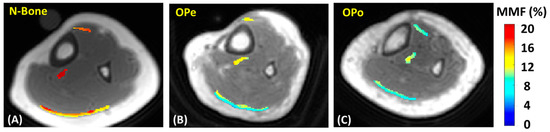

2.2. UTE-MRI Scanning

2.3. Data Analysis

3. Results